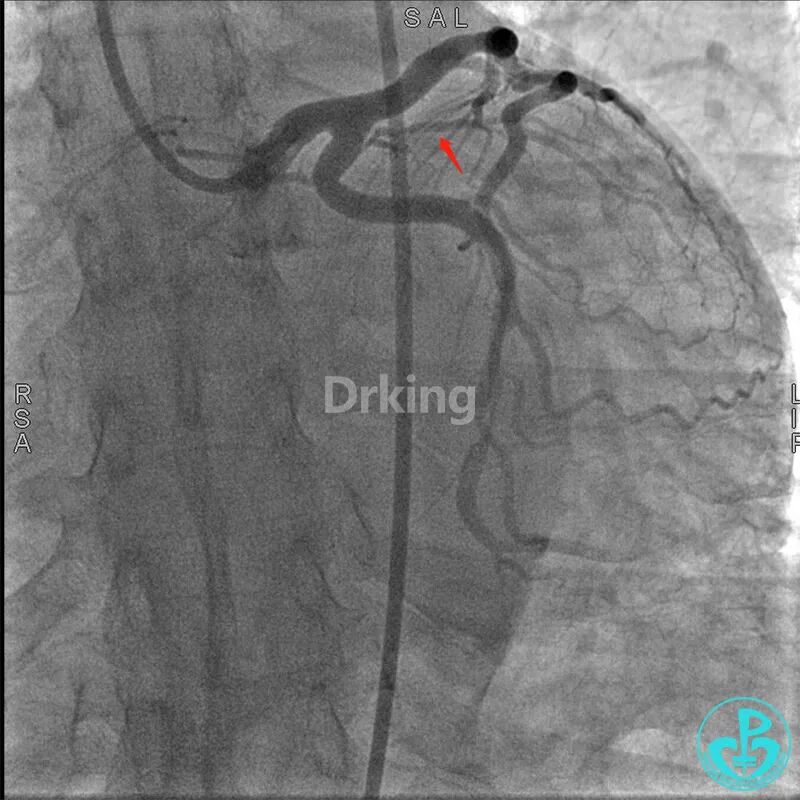

该患者于2019年03月28日在外院(县级市医院和地区级医学院附属大医院)两次冠脉造影术及PCI治疗均没成功,过程如下:

该患者近日转诊到江苏省人民医院,复查冠脉造影术,提示LCX近段扭曲严重(2处90度扭曲)的远段95%狭窄。当地医院市级及地区级医学院附属医院曾反复尝试,导丝均未能通过LCX近段扭曲处送至远段。